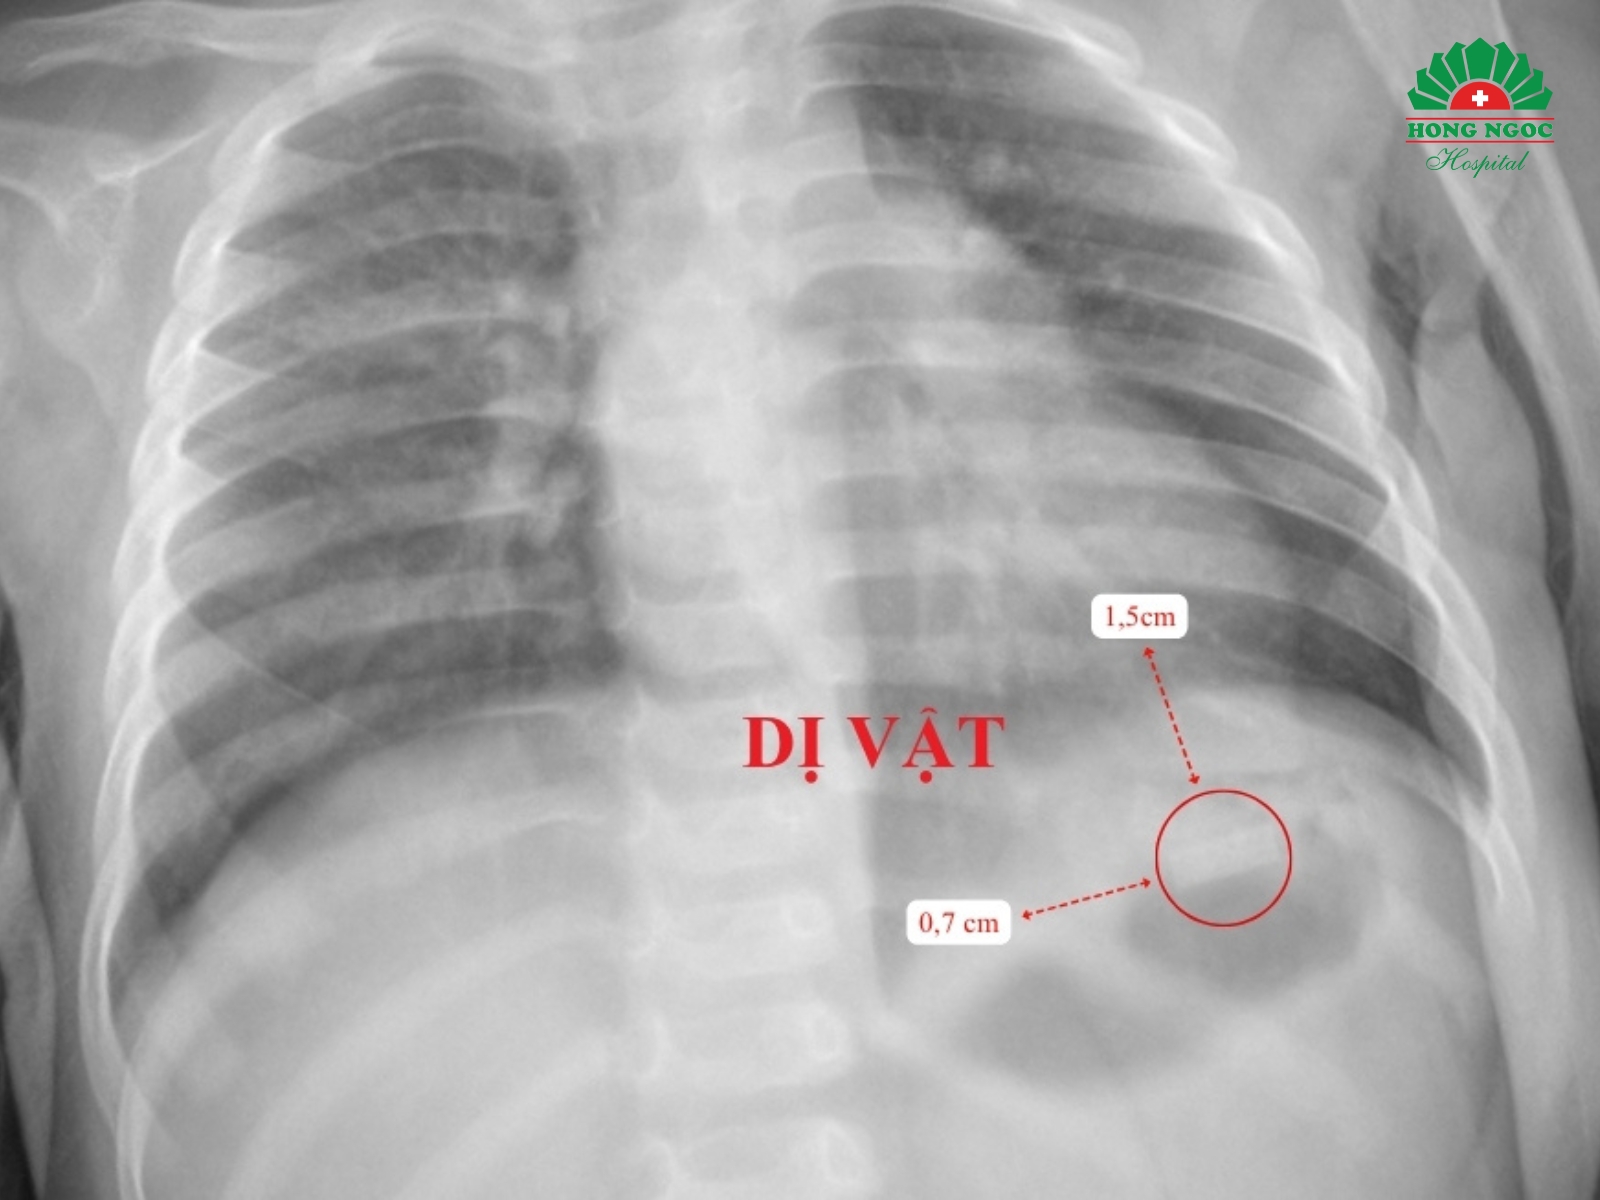

Tại Khoa Nhi - BVĐK Hồng Ngọc - Phúc Trường Minh, kết quả thăm khám lâm sàng và cận lâm sàng cho thấy một dị vật kim loại hình chữ nhật kích thước 1,5x0,7cm, có góc nhọn, mỏng và sắc như lưỡi dao nằm tại vùng hạ sườn trái, vị trí bóng hơi dạ dày của bé T. Ngoài ra, do nuốt phải một phần thuốc lá, trẻ có biểu hiện say thuốc với triệu chứng mệt mỏi, môi tái. Song, tình trạng này chỉ kéo dài khoảng 30 phút. Sau theo dõi, các chỉ số sinh tồn của bé ổn định, xét nghiệm máu không phát hiện bất thường.